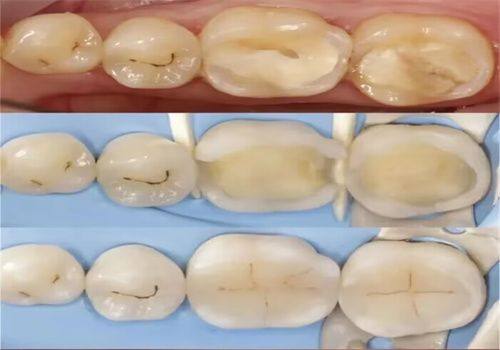

1. 特色儿童口腔科:配备专门的儿牙治疗医师与安抚医师,打造充满童趣的诊疗环境,儿童诊室牙椅采用卡通形象设计,能够有效缓解儿童看牙时的紧张恐惧情绪。可开展儿童龋病防治、牙髓治疗、早期错颌畸形干预等全品类儿童口腔诊疗项目,同时拥有传统活动矫治器、罗慕、ETA、正雅、时代天使、隐适美等多种早期干预矫治器,适配不同儿童牙齿畸形矫治需求。